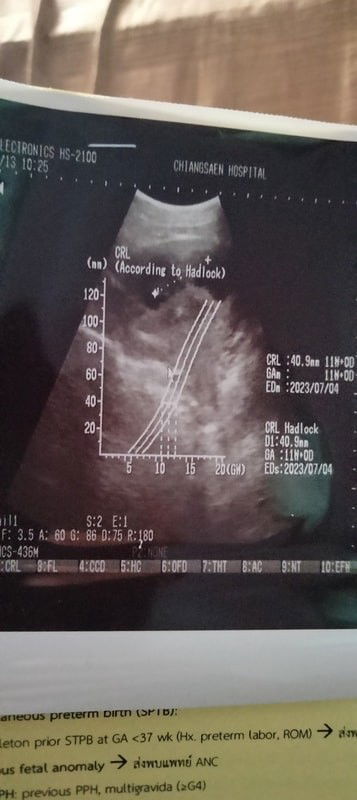

ตอนนี้ท้องได้11-12สัปดาห์แล้วค่ะท้องแรกด้วยแต่ท้องยังไม่ออกเลยและยังไม่เห็นการเปลี่ยนแปลงของท้องขึ้นเลยแล้วอีกอย่างอยากทราบว่าแม่ๆท่านใดพอมองออกบ้างค่ะน้องอยู่ตรงไหน

ตอนนี้ตั้งครรภ์ได้11-12สัปดาห์ฝากครรภ์ซาวด์เรียบร้อยแล้วหมอบอกน้องท้องในมดลูกปกติค่ะแต่ยังไม่ได้ยินเสียงหัวใจของน้องอันนี้ผิดปกติหรือป่าวค่ะไม่สบายใจเลย